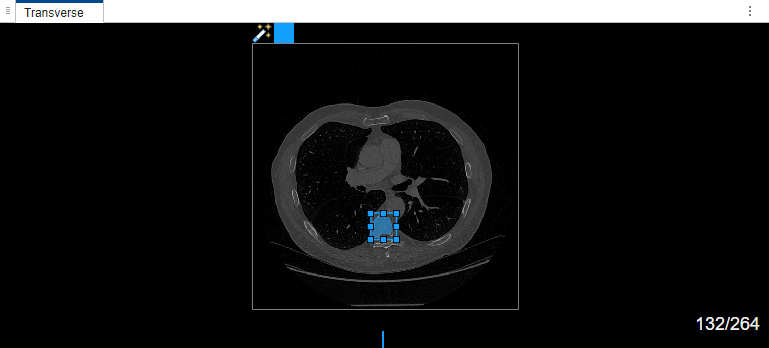

Select label Type1. Draw a bounding box around the object to segment in the transverse plane of the volume.

Once the MedSAM algorithm extracts the embeddings of the image, you can adjust the bounding box.